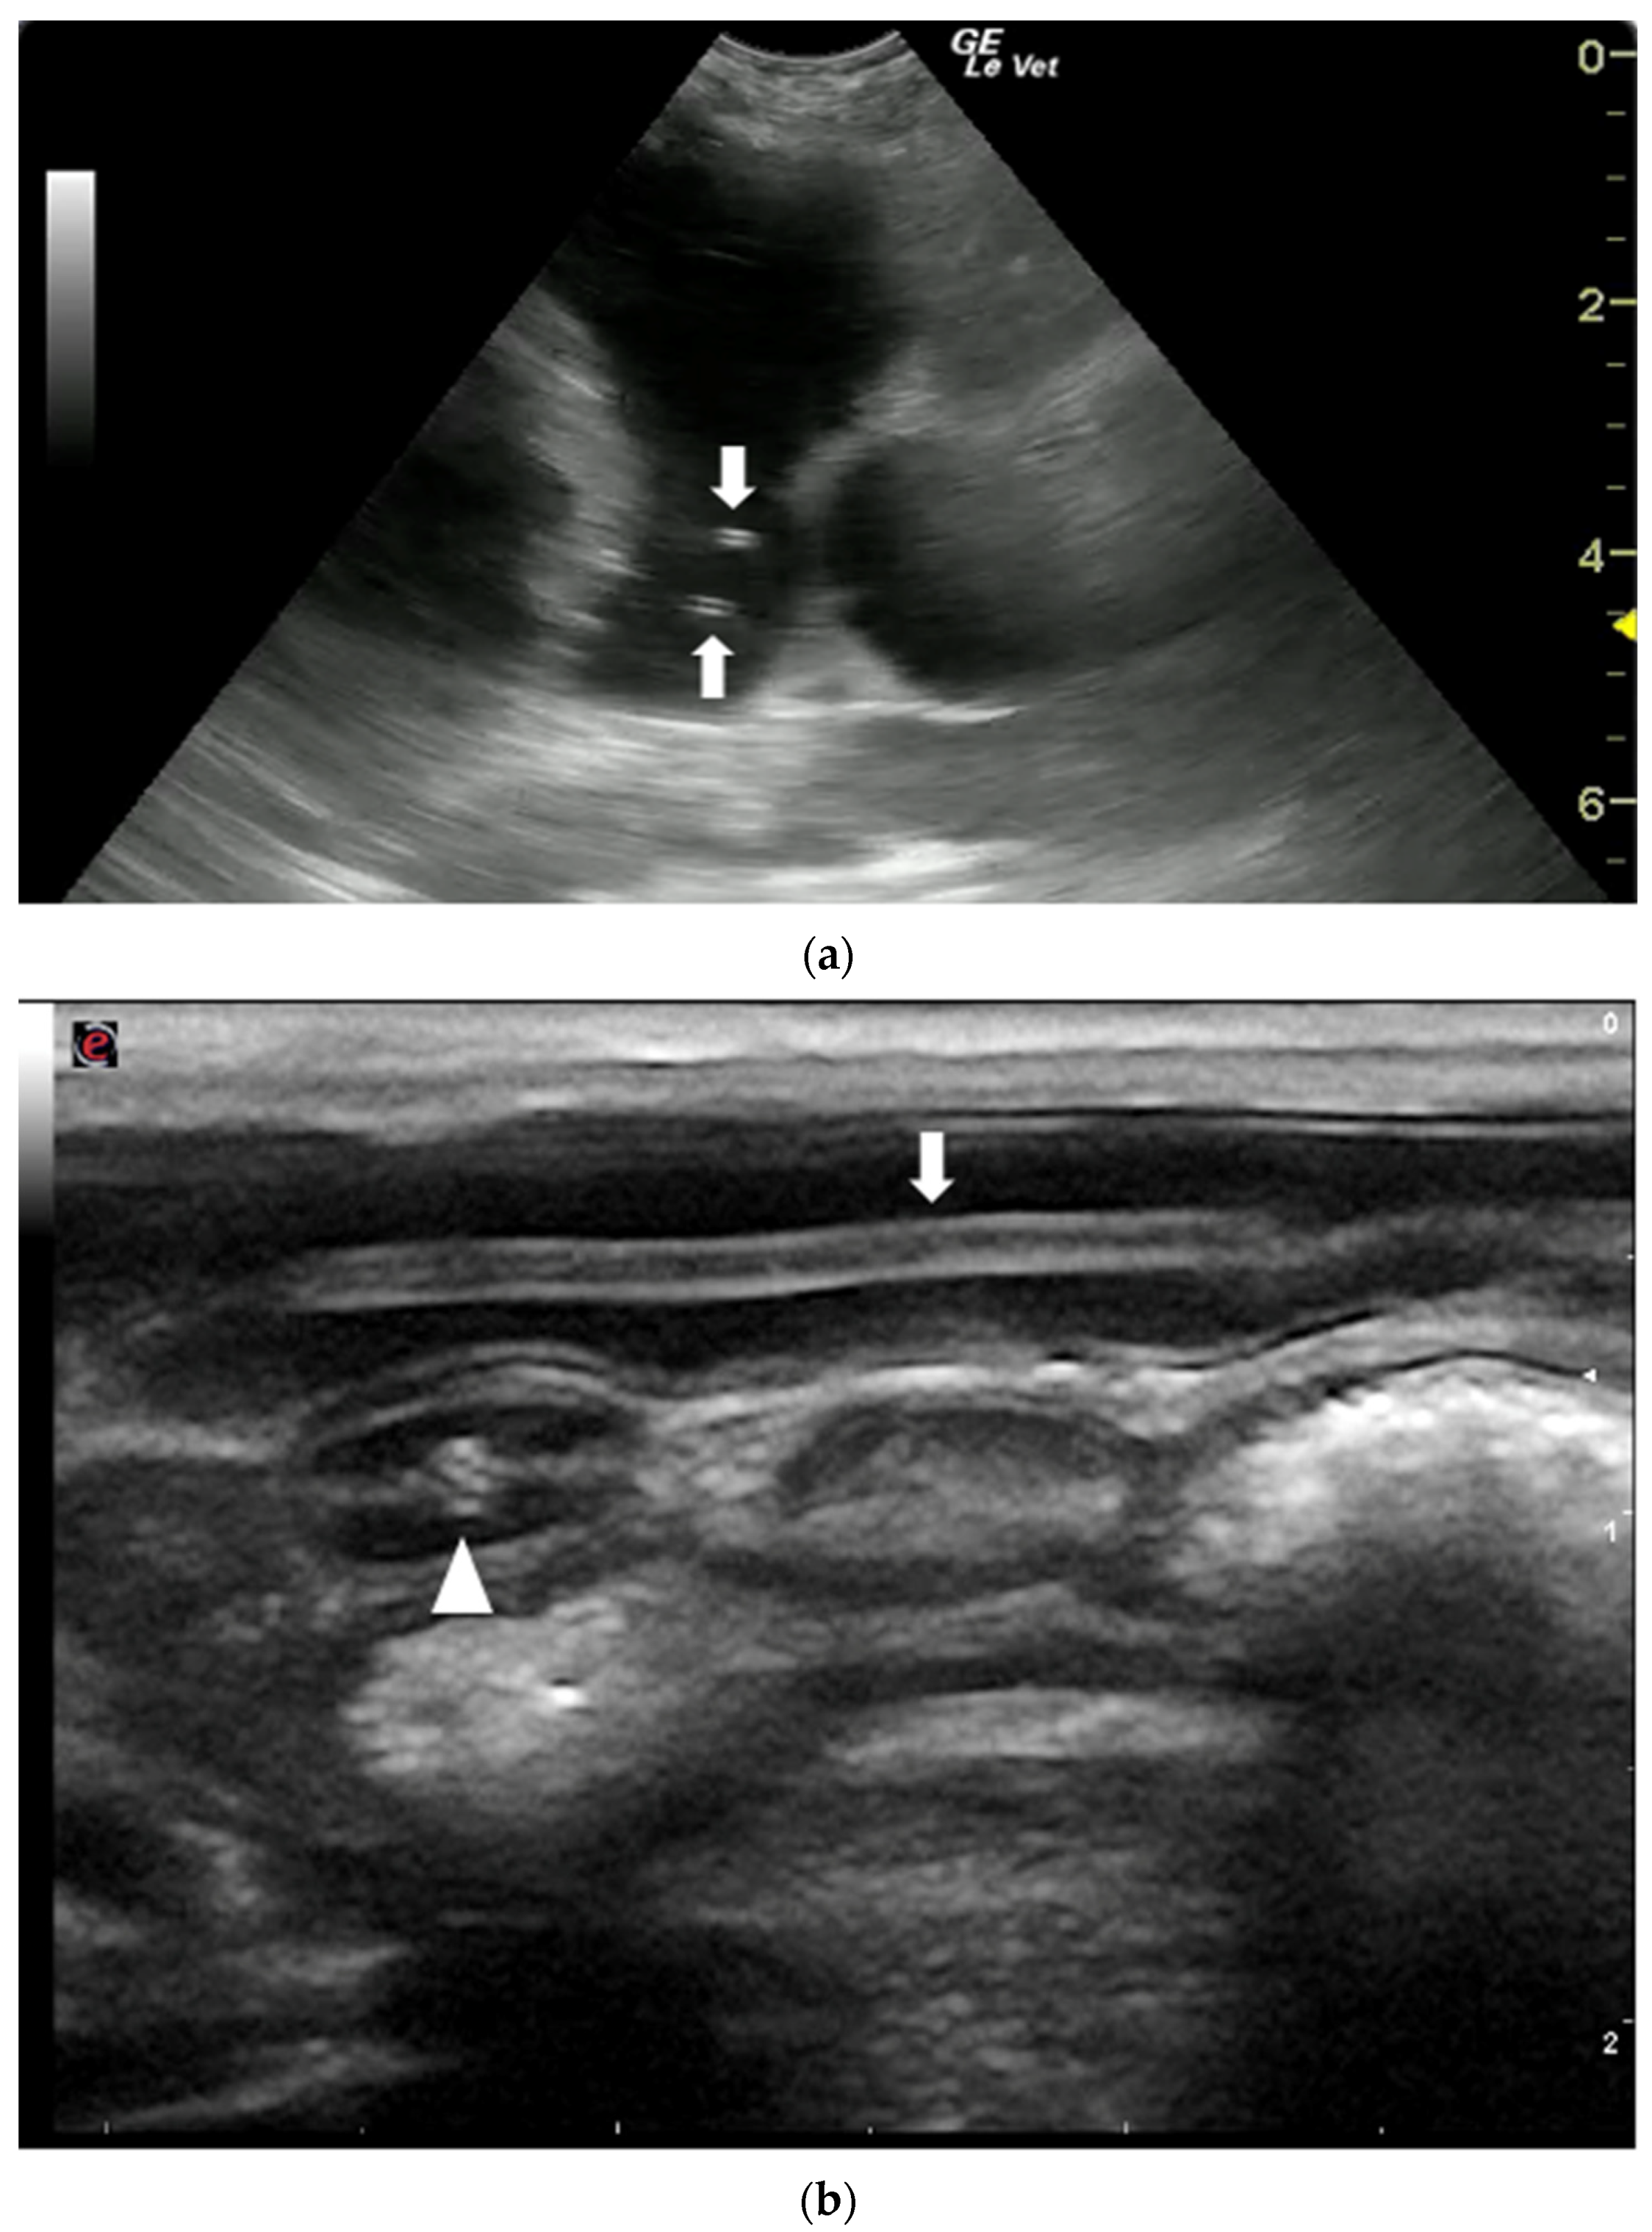

- Rahal, S.C.; Mamprim, M.J.; Oliveira, H.S.; Mesquita, L.R.; Faria, L.G.; Takahira, R.K.; Matsubara, L.M.; Agostinho, F.S. Ultrasonographic, computed tomographic, and operative findings in dogs infested with giant kidney worms (Dioctophyme renale). J. Am. Vet. Med. Assoc. 2014, 244, 555–558. [Google Scholar] [CrossRef]